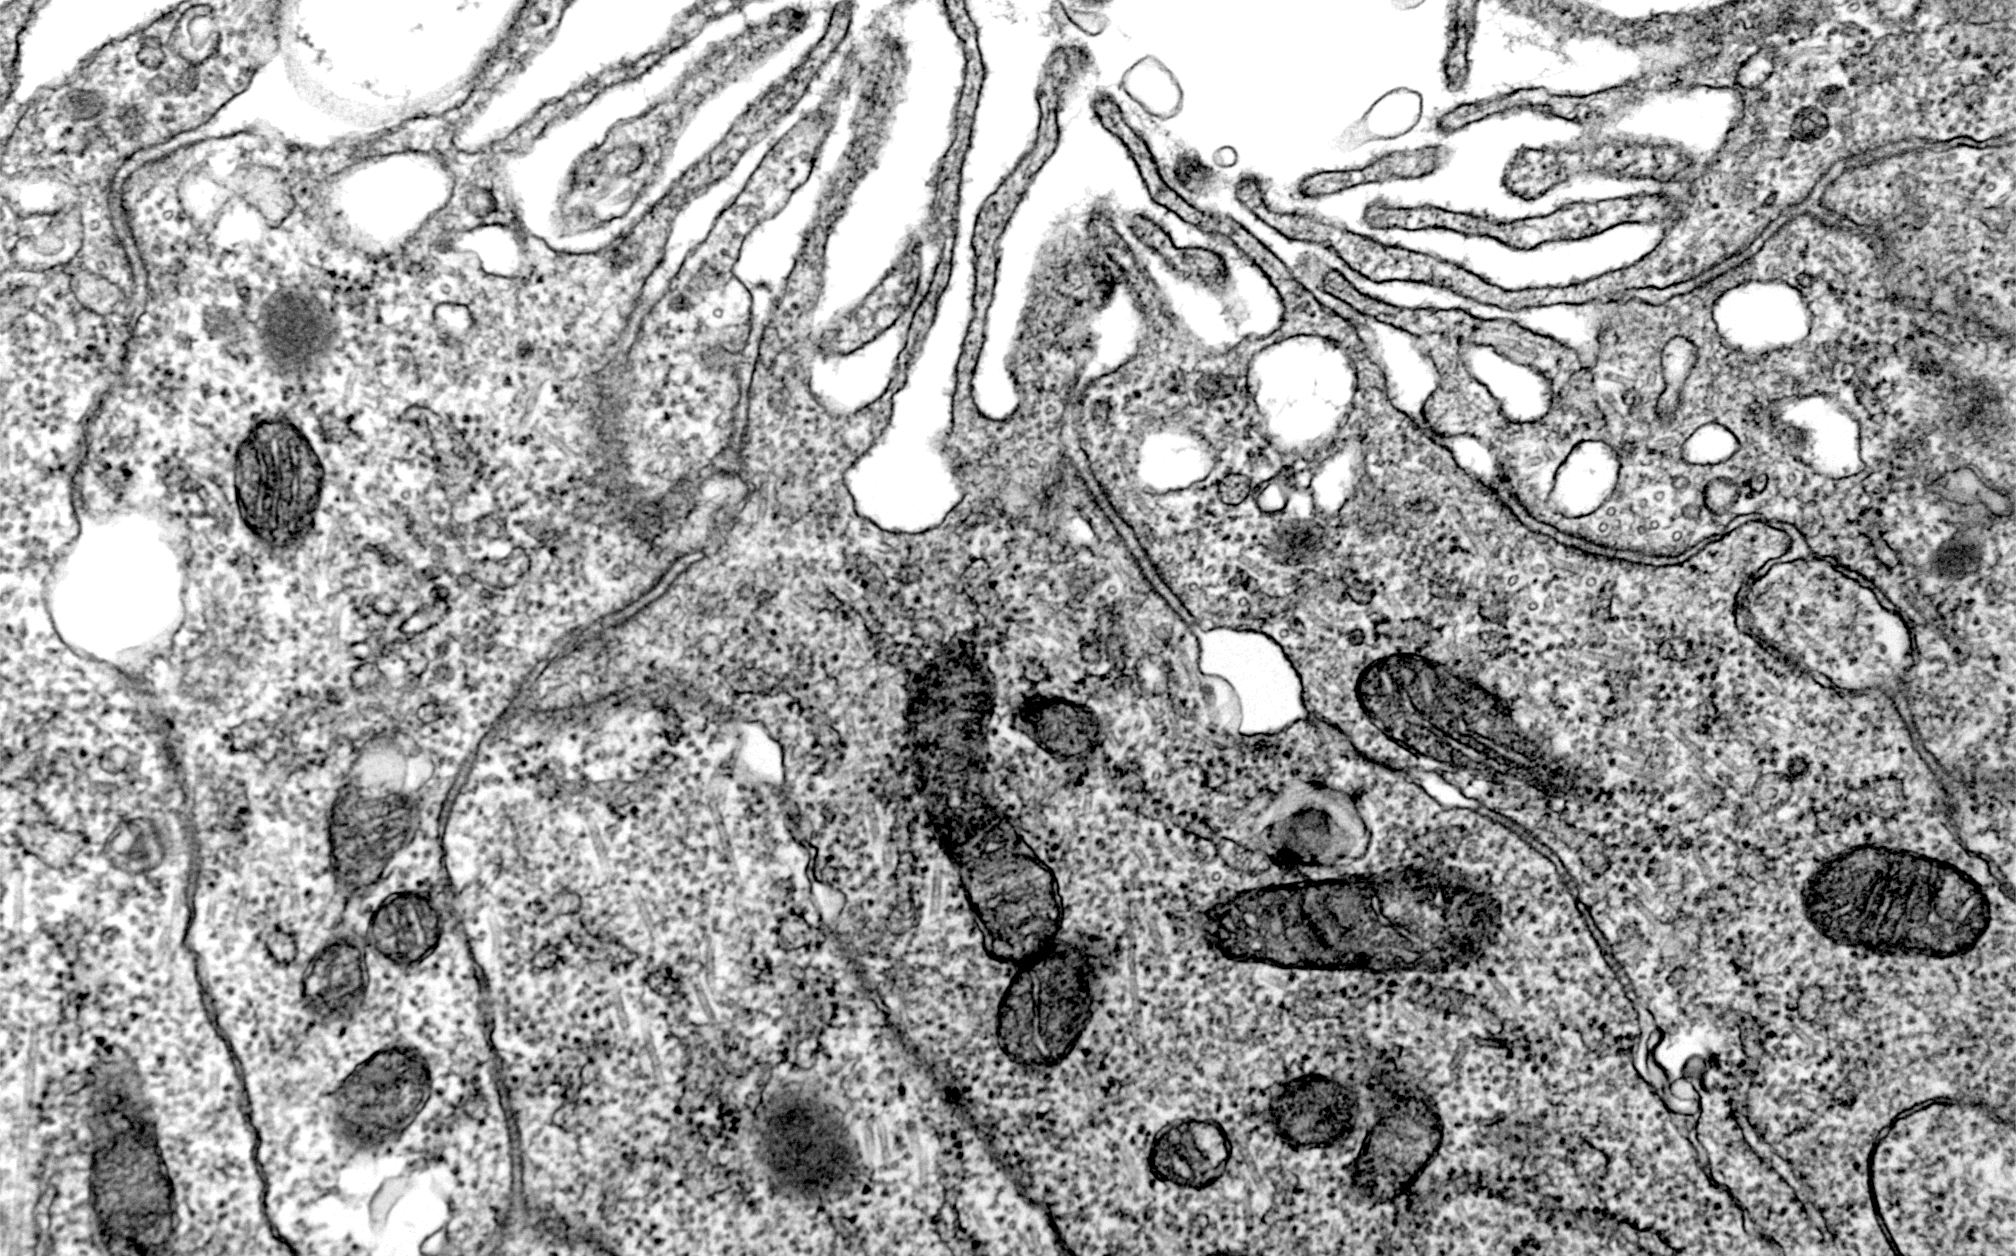

Micro-anatomy, classification and identification of vertebrate tissues.